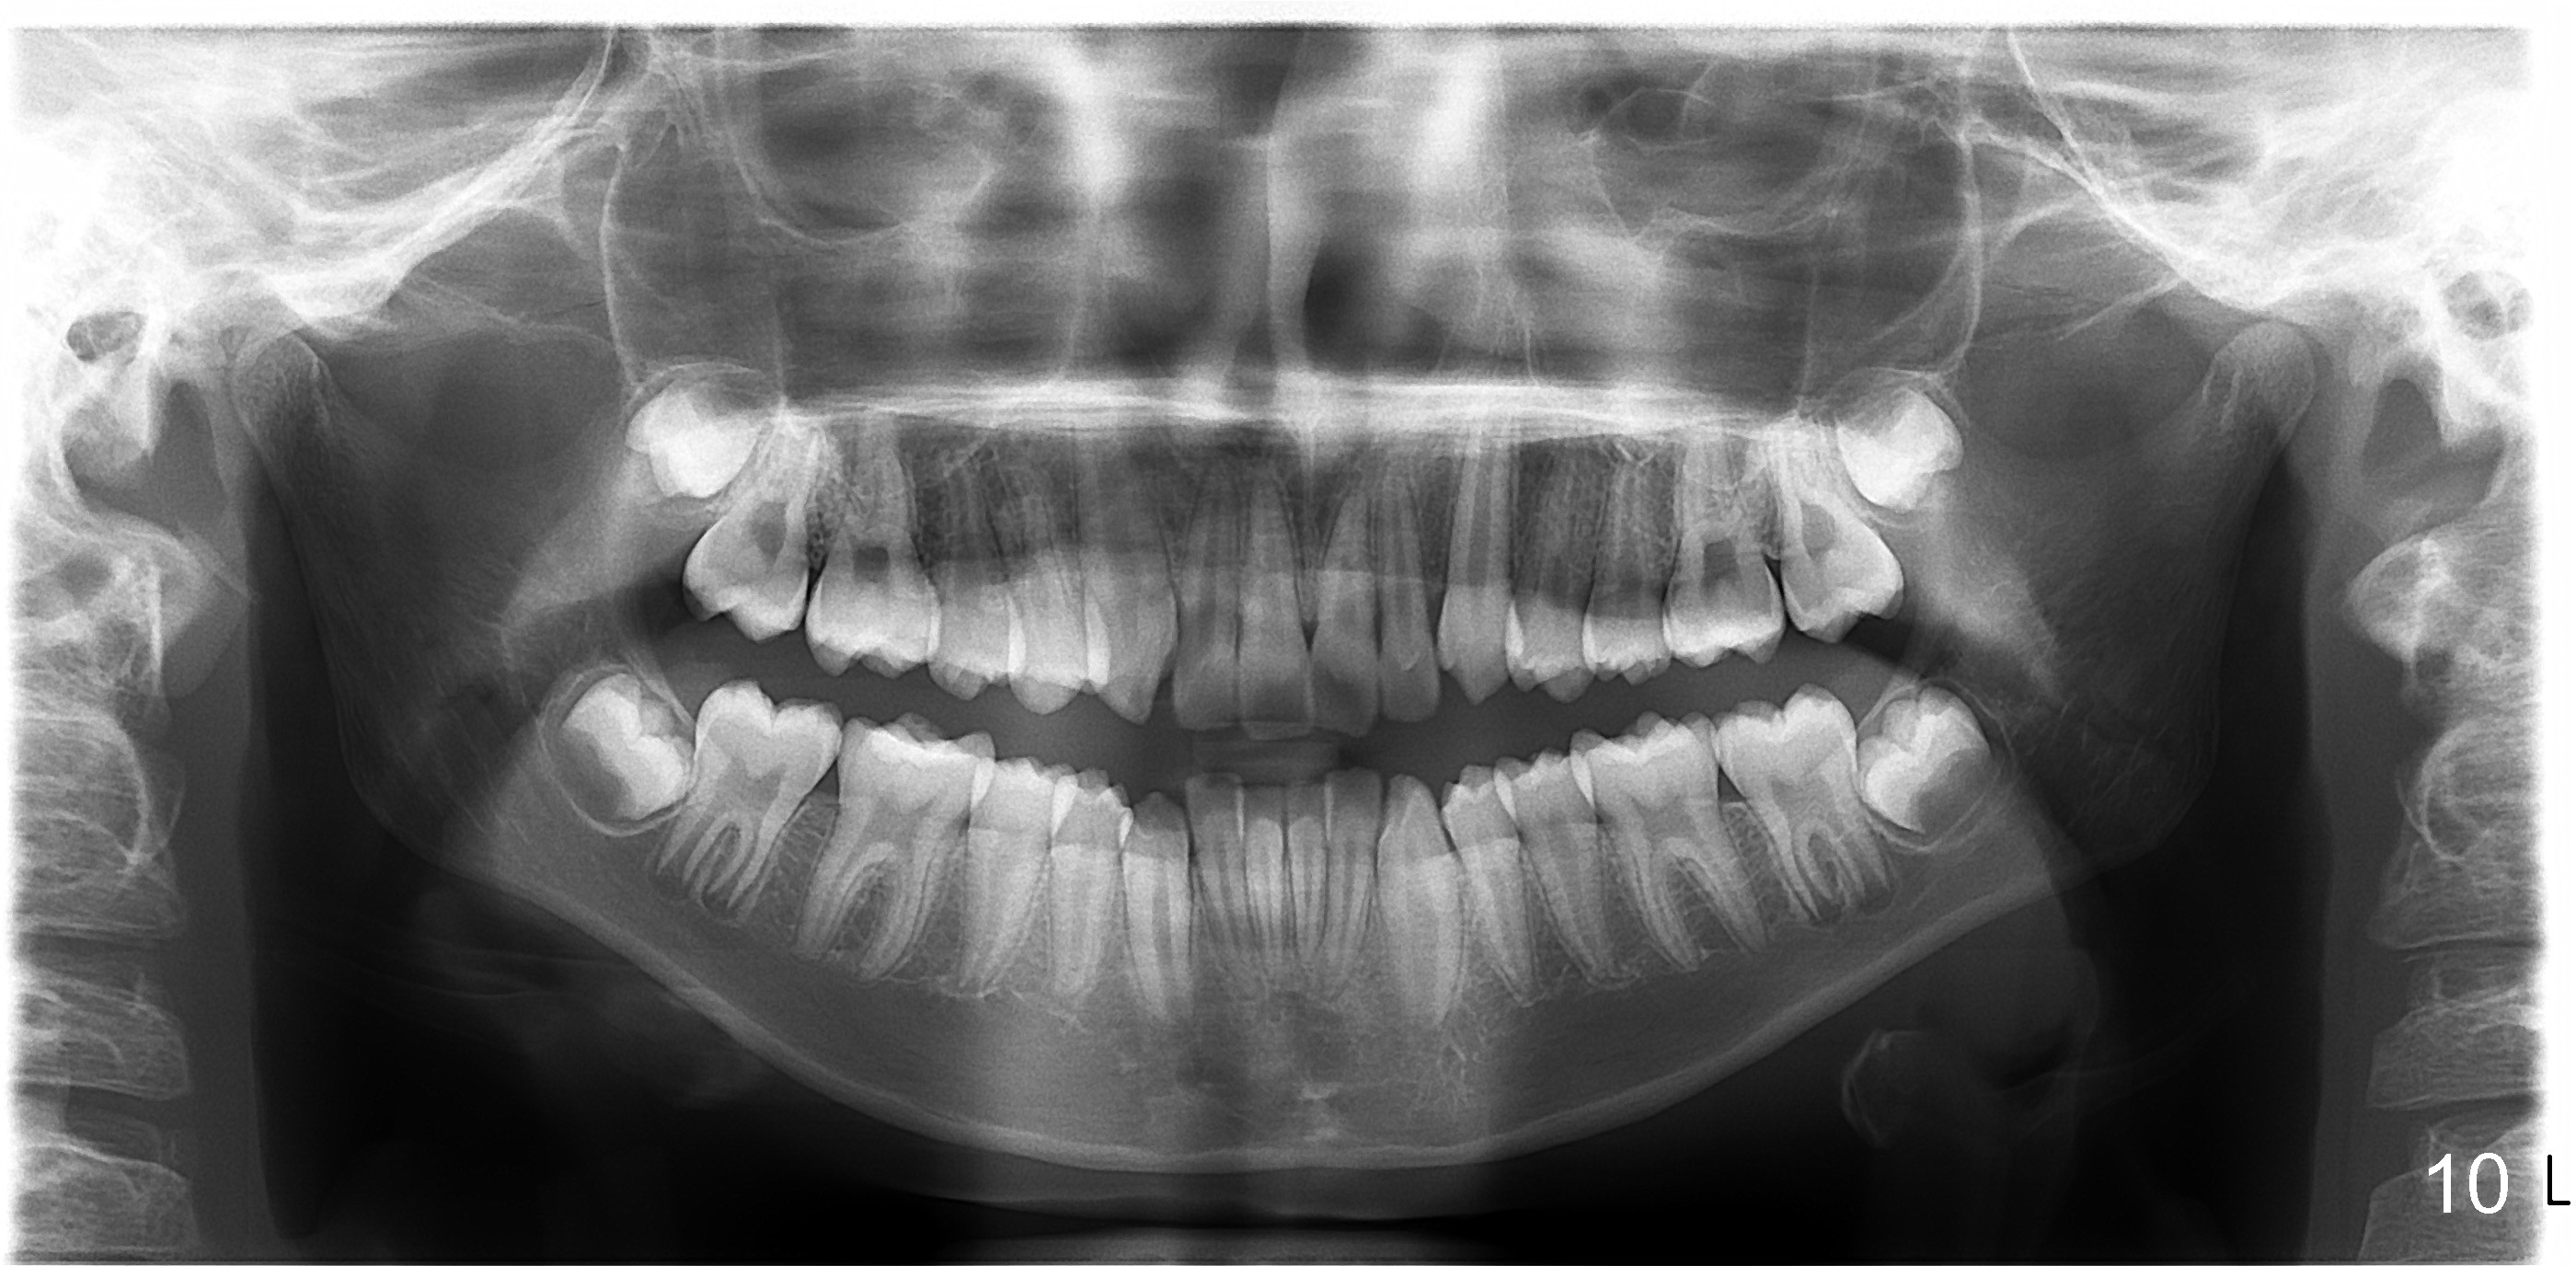

Photos were taken on May 29, 2012 (Fig.1-8), ceph and pan May 24, 2012 (Fig.9,10), post-extraction ceph July 30, 2012 (Fig.11).

I made the decision to extract 4 teeth because I thought the pt was too protrusive, lip incompetent. Non ext would make worse---simple as that!

I still place fixed retainer because I don't trust the teeth to stay, extraction or non.